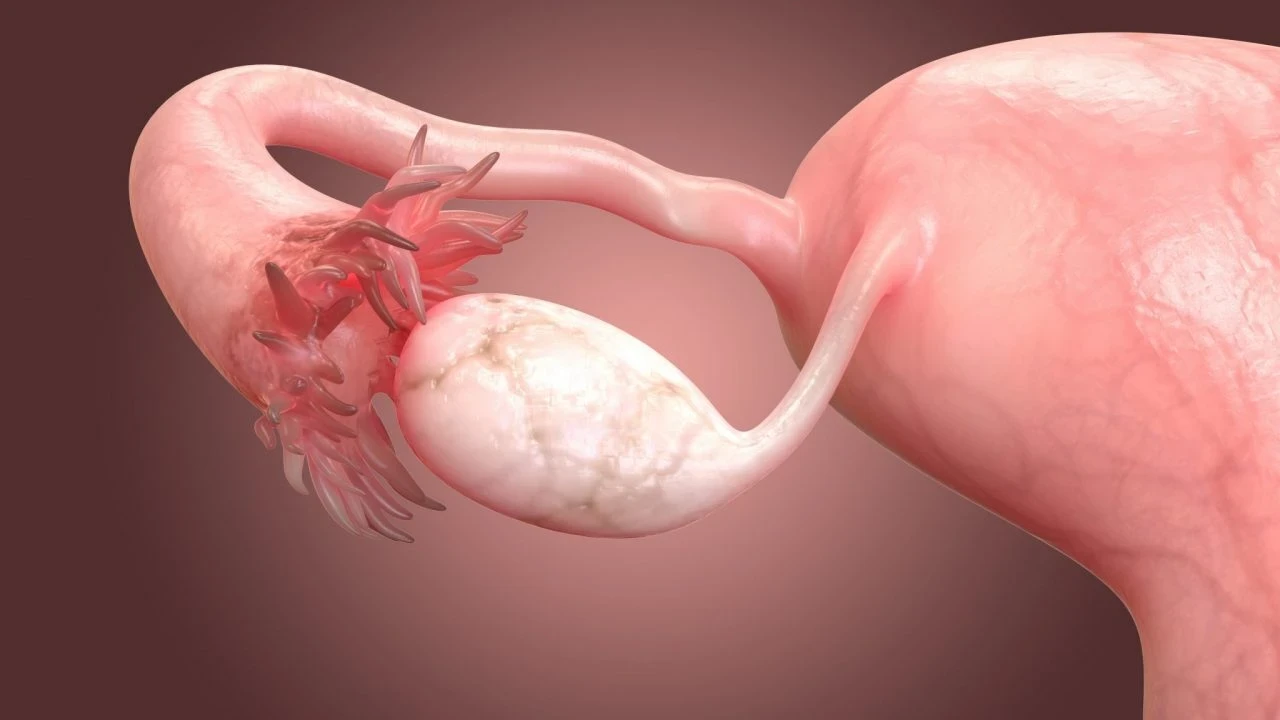

Yumurtalık zayıflığı, tıbbi adıyla primer over yetmezliği, yumurtalıkların yeterli düzeyde yumurta üretememesi ya da yumurtlama döngüsünü sağlıklı bir şekilde sürdürememesi durumudur. Bu durum, kadınların hormonal dengelerini de etkileyerek östrojen seviyelerinin düşmesine yol açabilir. Yumurtalık zayıflığı, menopozdan farklıdır çünkü bu durumdaki kadınlar hala düzensiz de olsa adet görebilir ve nadiren de olsa doğal yolla hamile kalabilir.

Yumurtalık Zayıflığının Belirtileri

- Kısırlık: Doğurganlık kapasitesinin azalması.